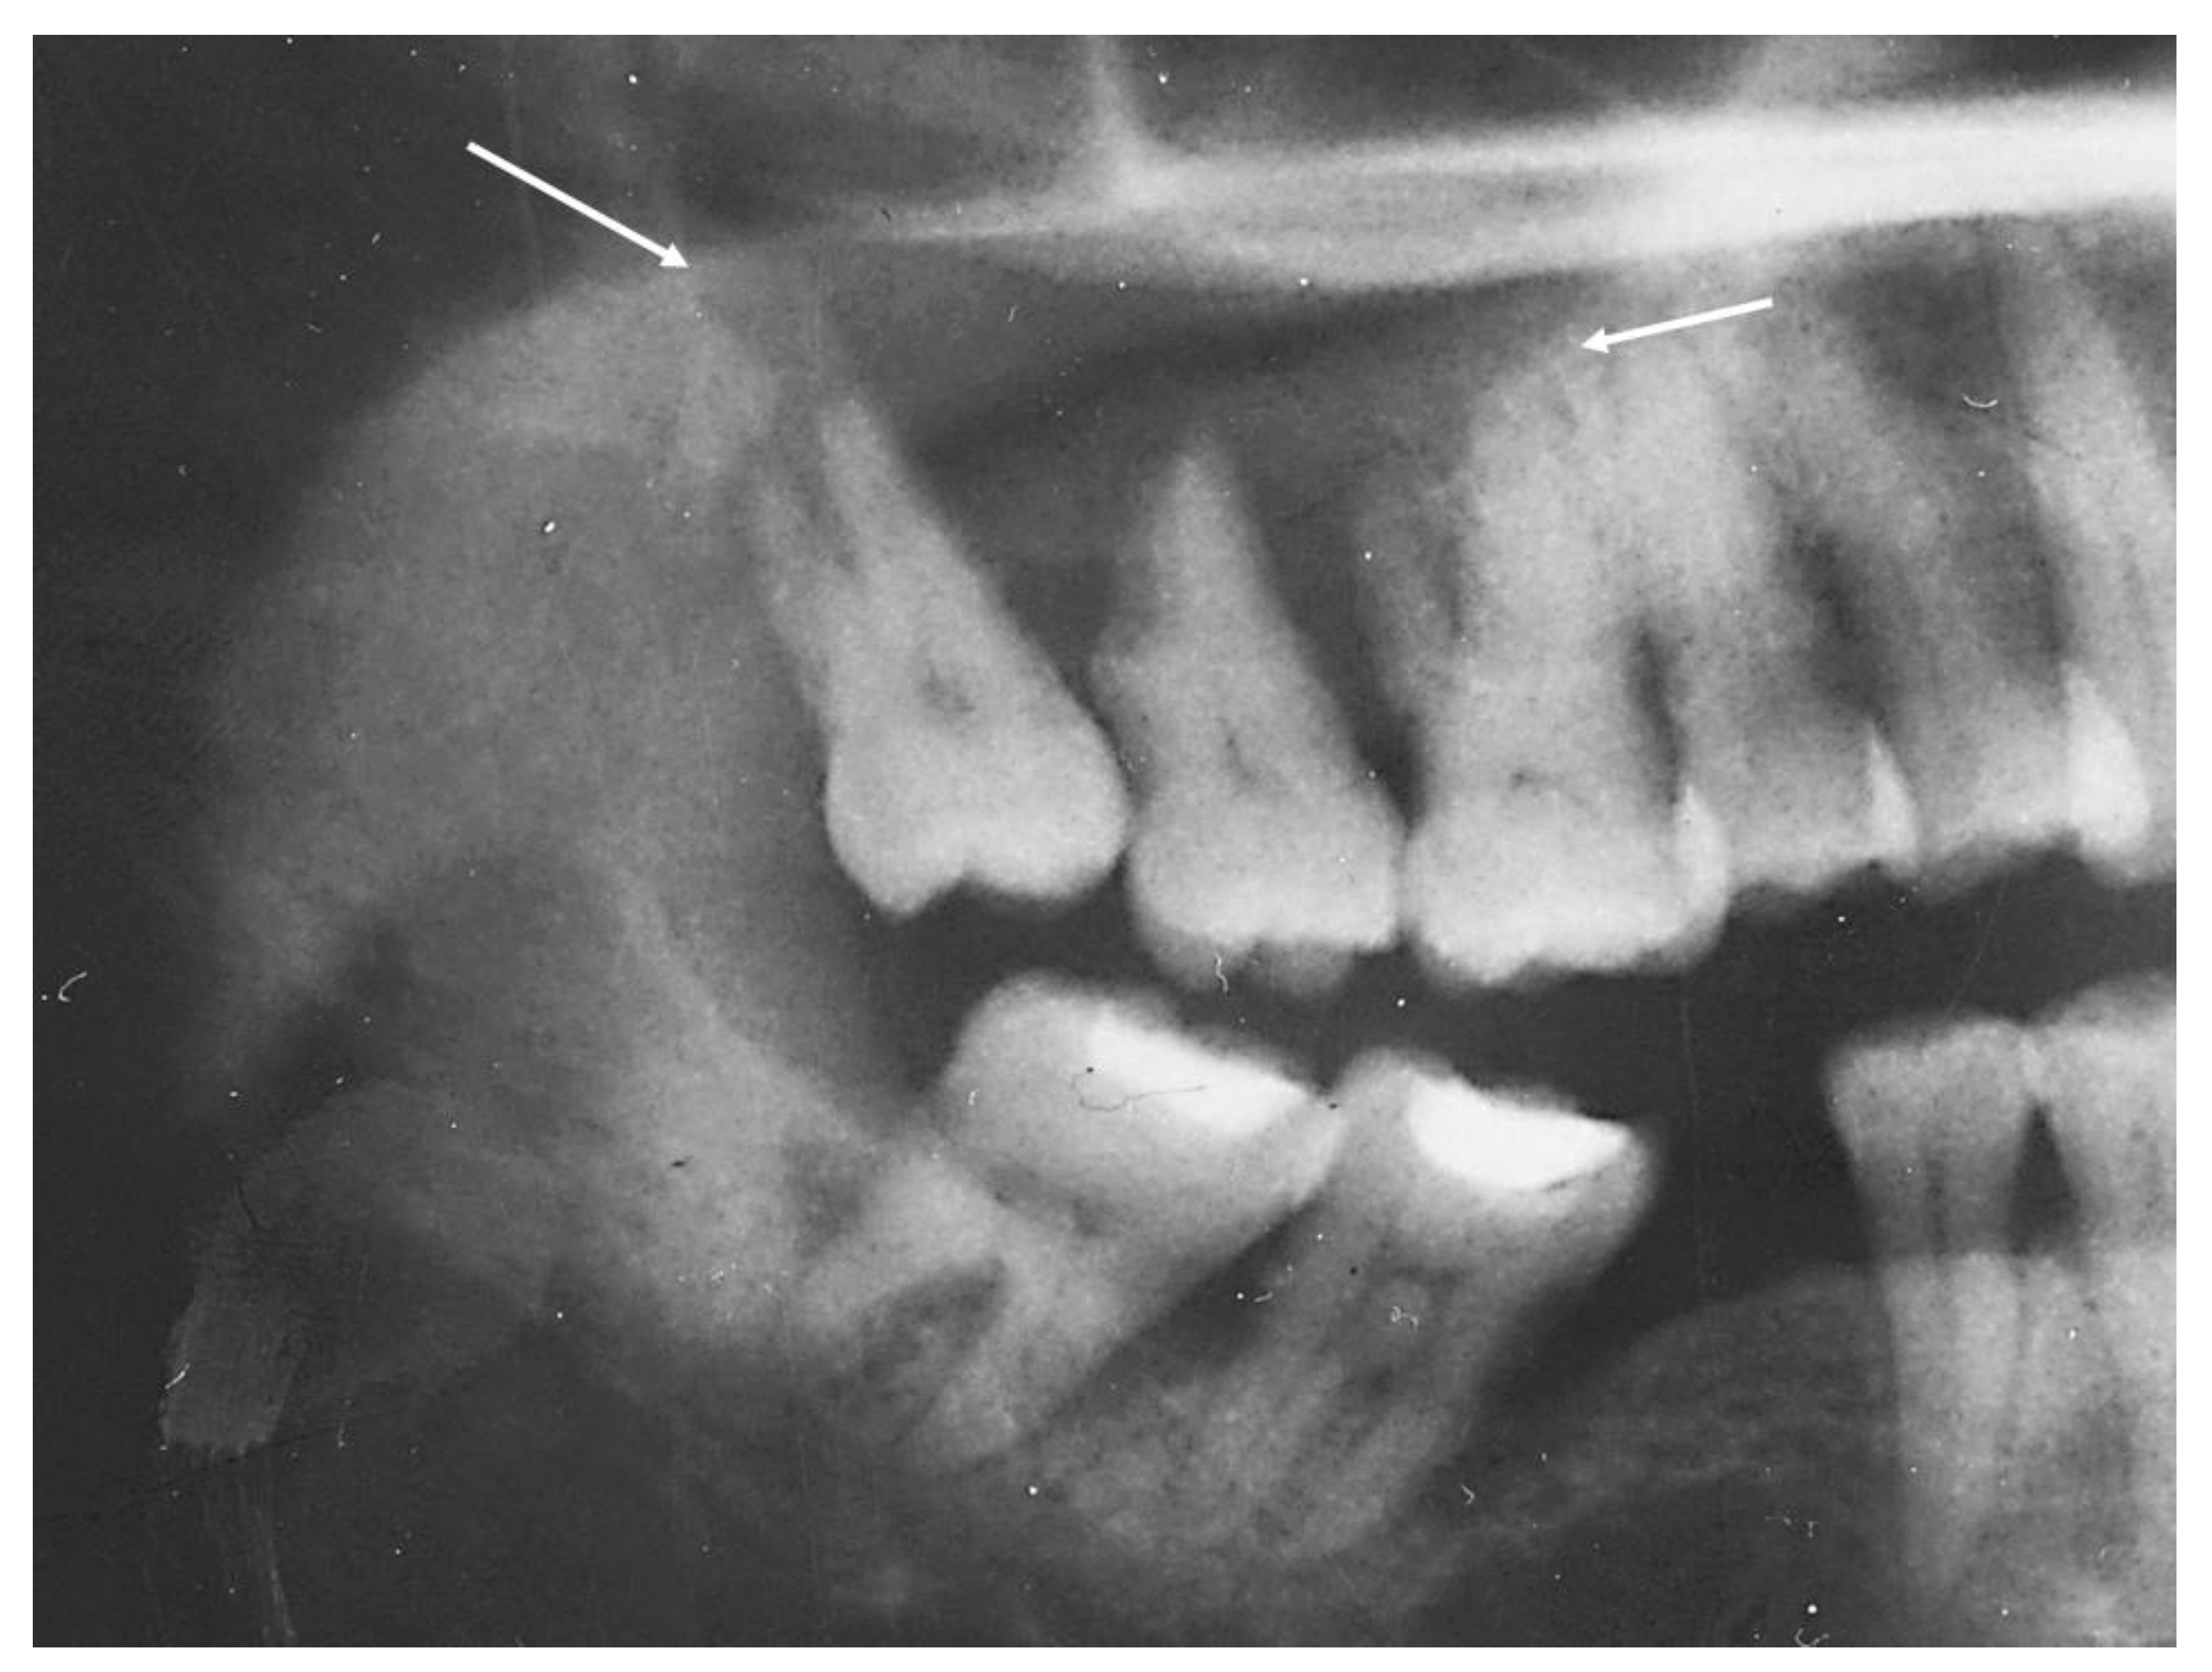

2.1. Case 1